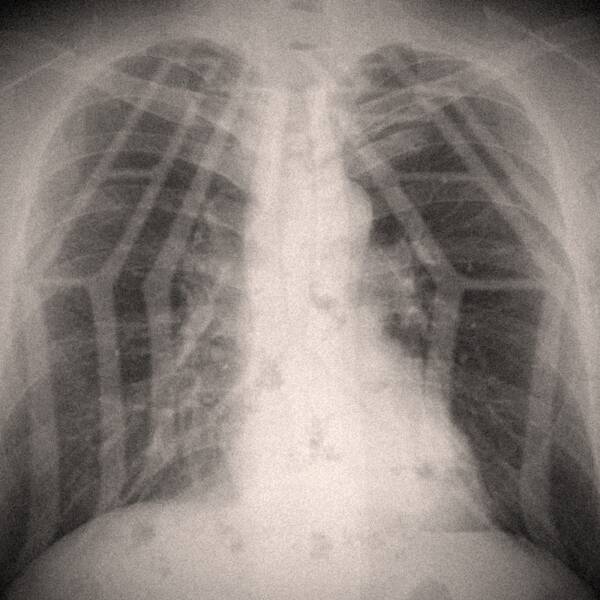

おおくぼけい:実は僕、人よりも肋骨が一本多いんですよ。けっこうそういう人っているらしくて。

おおくぼけい:いや、どっちかですね。昔、ヤンキーに絡まれて蹴られて、病院に行ってレントゲンを撮ったら「肋骨が一本多いですね」と医者に言われたんですよ。自分でもこれは面白い、『創世記』的に言えばここにイブがいるんじゃないか? と思って(笑)。

マリアンヌ東雲:おおくぼ君のそんな話を聞いて、そういえばワタクシも原爆スター階段のライブを最前列で観て肋骨にヒビが入ったことがあるわよなんて話をしたんですよ。それでユニット名は肋骨にしようかということになりまして。

おおくぼけい:後付けになりますけど、たとえば船の骨格も肋骨ですよね。即興演奏はその人の素が出るものだし、自分の身に普段まとわりついてるいろんなものを外した骨組みが自然と出たものじゃないかと。